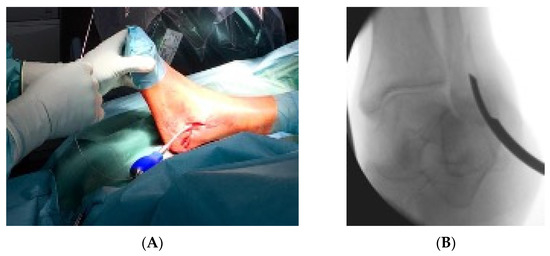

2.2. Surgical Technique and Postoperative Therapy